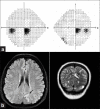

Visual field assessment is important in the evaluation of lesions involving the visual pathways and should be performed at baseline and periodically in the follow-up. Standard automated perimetry has been shown to be adequate in neuro-ophthalmic practise and is now the technique of choice for a majority of practitioners. Goldman kinetic visual fields are useful for patients with severe visual and neurologic deficits and patients with peripheral visual field defects. Visual fields are useful in monitoring progression or recurrence of disease and guide treatment for conditions such as idiopathic intracranial hypertension (IIH), optic neuropathy from multiple sclerosis, pituitary adenomas, and other sellar lesions. They are used as screening tools for toxic optic neuropathy from medications such as ethambutol and vigabatrin. Visual field defects can adversely affect activities of daily living such as personal hygiene, reading, and driving and should be taken into consideration when planning rehabilitation strategies. Visual field testing must be performed in all patients with lesions of the visual pathway.